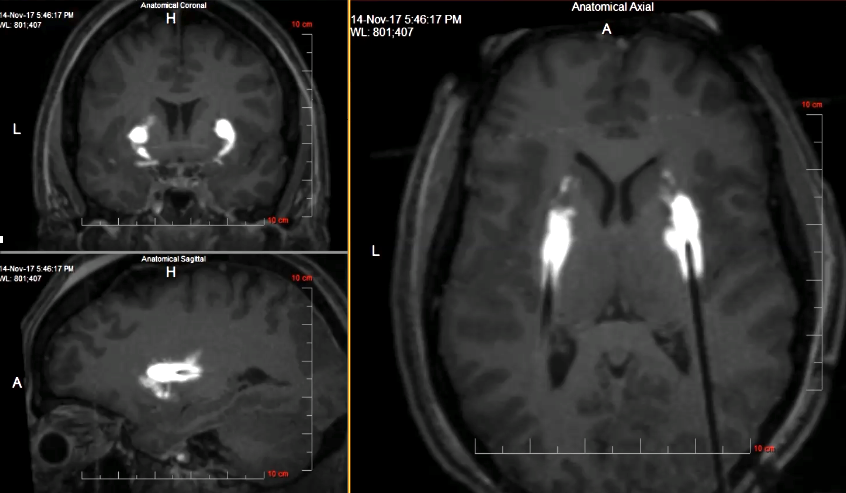

Deep Brain Stimulation for OCD

Deep Brain Stimulation for Movement Disorders